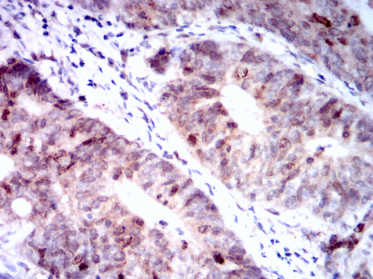

AURKB Mouse Monoclonal antibody[13E8D]

AURKB (aurora kinase B, AIK2 or aurora-B), with 344-amino acid protein(about 39kDa),localizes to microtubules near kinetochores, specifically to the specialized microtubules called K-fibers. AURKB is a mitotic protein kinase, which phosphorylates histone H3 and regulates Chromosomal segregation during mitosis and meiosis.It may regulates several stages of mitosis such as centrosome separation, chromosome segregation and cytokinesis.Component of the chromosomal passenger complex (CPC), a complex that acts as a key regulator of mitosis. The CPC complex has essential functions at the centromere in ensuring correct chromosome alignment and segregation and is required for chromatin-induced microtubule stabilization and spindle assembly. ARK-2 transcripts arepresent at high levels in human thymus and fetal liver.ARK-2 protein levels are maximal during both S and G2/M phases

IHC    1/200 - 1/1000